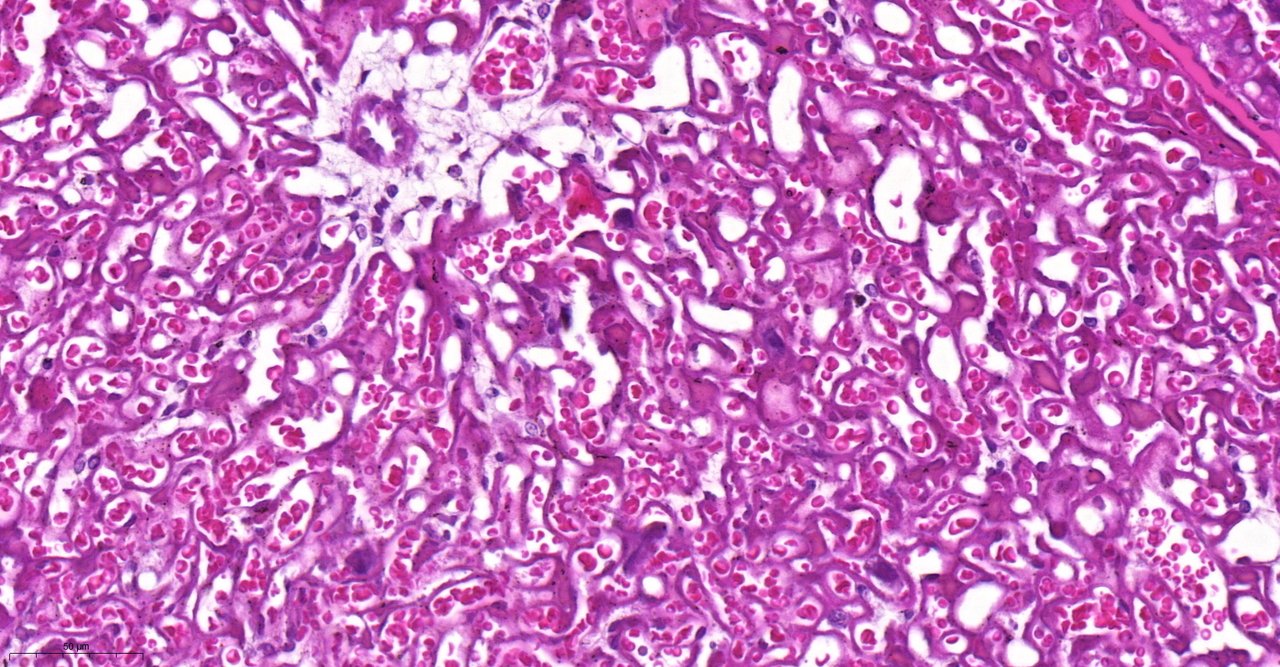

O objetivo do estudo foi avaliar como diferentes tipos de infecções alteram os transportadores ABC e se essa alteração poderia ser um dos desencadeadores ou fator coadjuvante para o parto prematuro. Para isso, a equipe utilizou modelos de placentas de camundongos fêmeas infectadas por malária, bactéria e vírus da Zika. No último caso, foi possível pesquisar também a presença dos transportadores em placenta humana. Em todas as situações, os pesquisadores observaram que houve diminuição desses dois transportadores na membrana das células da placenta. “Isso é bom ou ruim? É para preservar o feto ou leva a um acúmulo de toxinas que desencadeiam o parto antes do tempo? Ainda não sabemos e precisamos de mais estudos”, afirma Tânia.